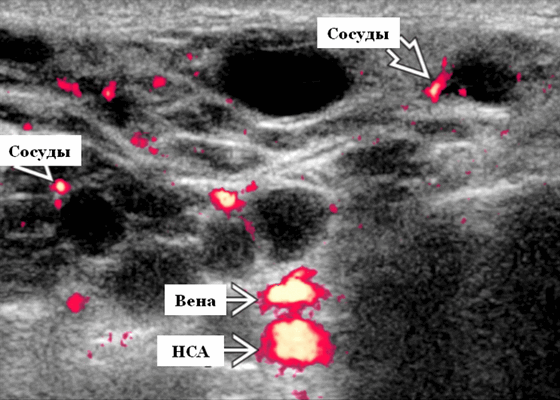

- Цветной допплер. Кистозные поражения: от бессосудистого до умеренного сосудистого кровотока в перегородках, интрамуральных лимфоузлах и на периферии. Смешанные поражения: переменная, васкуляризация от легкой до умеренной. Солидные поражения: внутрипаротидная васкуляризация.

- Серошкальное УЗИ. Спектр сонографических находок от простых кист до смешанных и солидных образований. Кистозные, смешанные и солидные поражения могут возникать одновременно в околоушных железах. Кистозные поражения (кисты ДЛК). Хорошо очерченная киста, разного размера, от анэхогенной до гипоэхогенной структуры с задним акустическим усилением. Сеть тонких перегородок ± муральные узлы. Часто встречаются внутренние эхо, которые могут быть мобильными. Сотовидная внешность паренхимы околоушной железы, когда она диффузно изменена з а счет кист. Смешанные поражения (ДЛП). Границы могут быть плохо очерченными, разного размера. Структура преимущественно гипоэхогенная, железы могут быть неоднородными. Без заднего акустического усиления. Солидные поражения (околоушная лимфаденопатия). Множественные овальные / круглые, гипоэхогенные, внутрипаротидные лимфоузлы на УЗИ. Четкий корковый слой ± сохранная корневая архитектура. Сопутствующая реактивная шейная лимфаденопатия

Энергетический допплер. Внутриочаговая васкуляризация. Хаотический / дезорганизованный или преимущественно периферический кровоток

- Интранодулярный кровоток хаотичный / дезорганизованный или преимущественно периферический